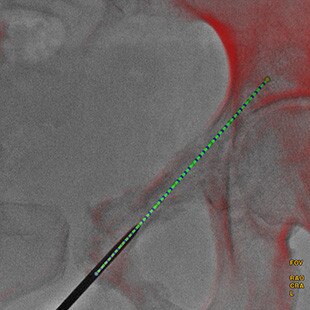

EMBOLISATION PERCUTANÉE DES ENDOFUITES DE TYPE II

Guider